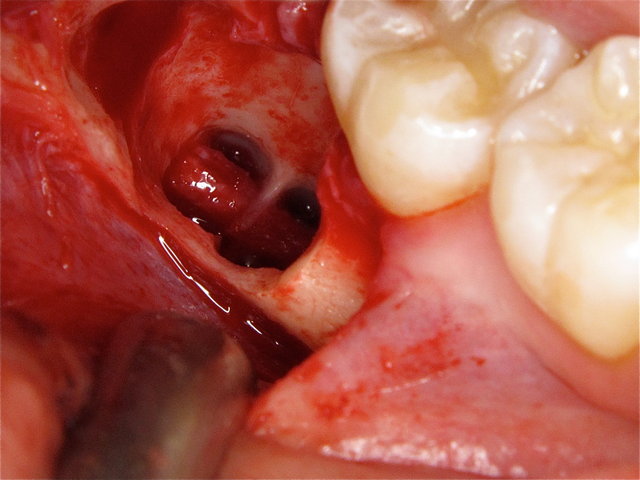

Sichtbarer Nerv im Zahnfach